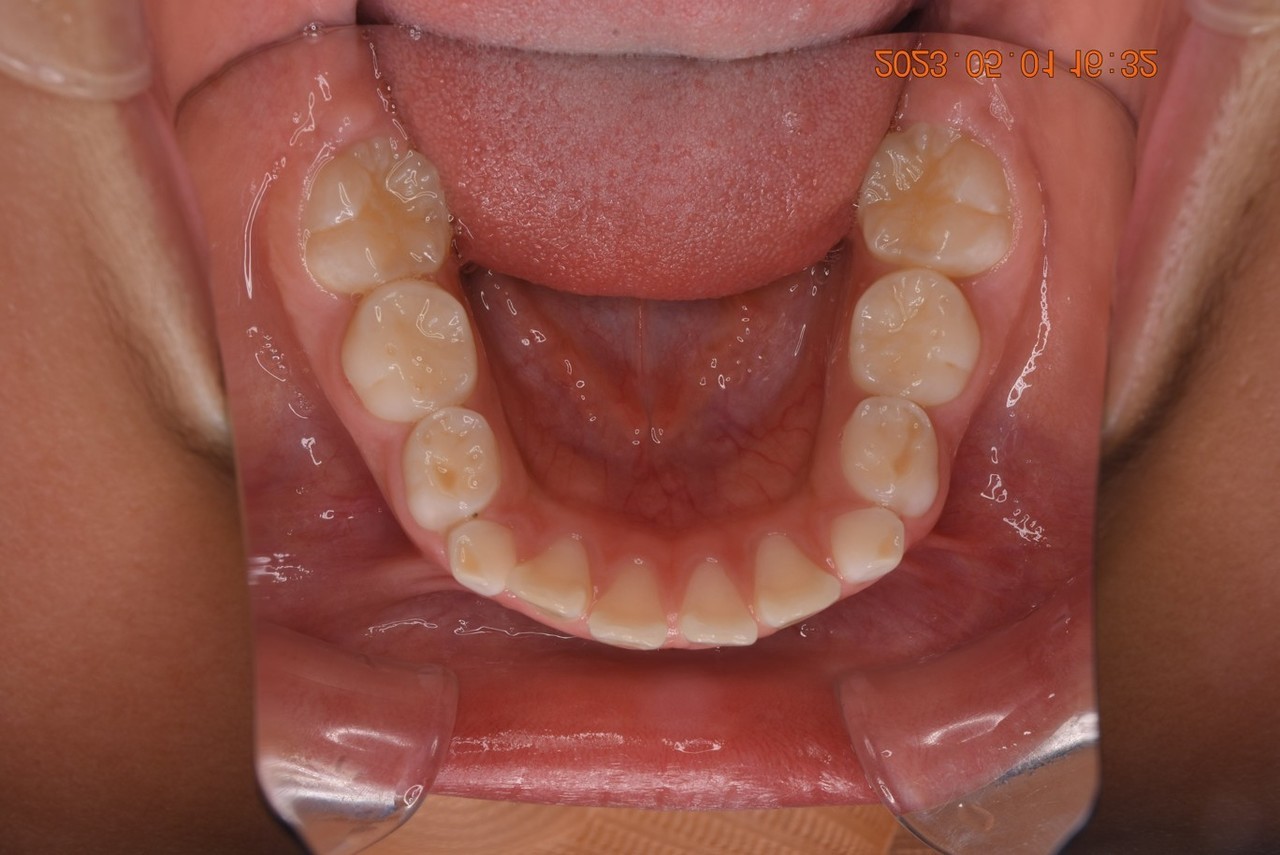

03:ガタガタ(叢生)の歯並びだった方

ガタガタ・叢生の歯並びの矯正治療前

ガタガタ・叢生の歯並びの矯正終了後

保定(リテーナー)

症例・治療内容について

• 主訴:ガタガタしている

• 診断あるいは主な症状:開口

• 年齢:31歳(治療開始年齢)

• 治療に用いた主な装置:マルチブラケットによる歯列矯正

• 抜歯部位:なし

• 治療期間:1年10ヶ月

• 通院回数:25回(矯正治療を目的とした来院)

• 治療費概算:875,000円(税込)